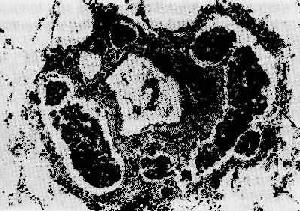

(3)浸润性生长:为大多数恶性肿的生长方式。细胞分裂增生,侵入周围组织间隙、淋巴管或血管内,如树根之长入泥土,浸润并破坏周围组织。因而此类肿没有包膜,与邻近的正常组织紧密连接在一起而无明显界限(图7-4)。临床触诊时,肿固定不活动。手术切除这种肿时,切除范围比肉眼所见肿范围为大,因为这些部位也可能有肿细胞的浸润。

图7-4 恶性肿的浸润性生长(食管鳞状细胞

细胞形成大小、形状不一的细胞巢,浸润于管壁组织(包括肌层)间隙内